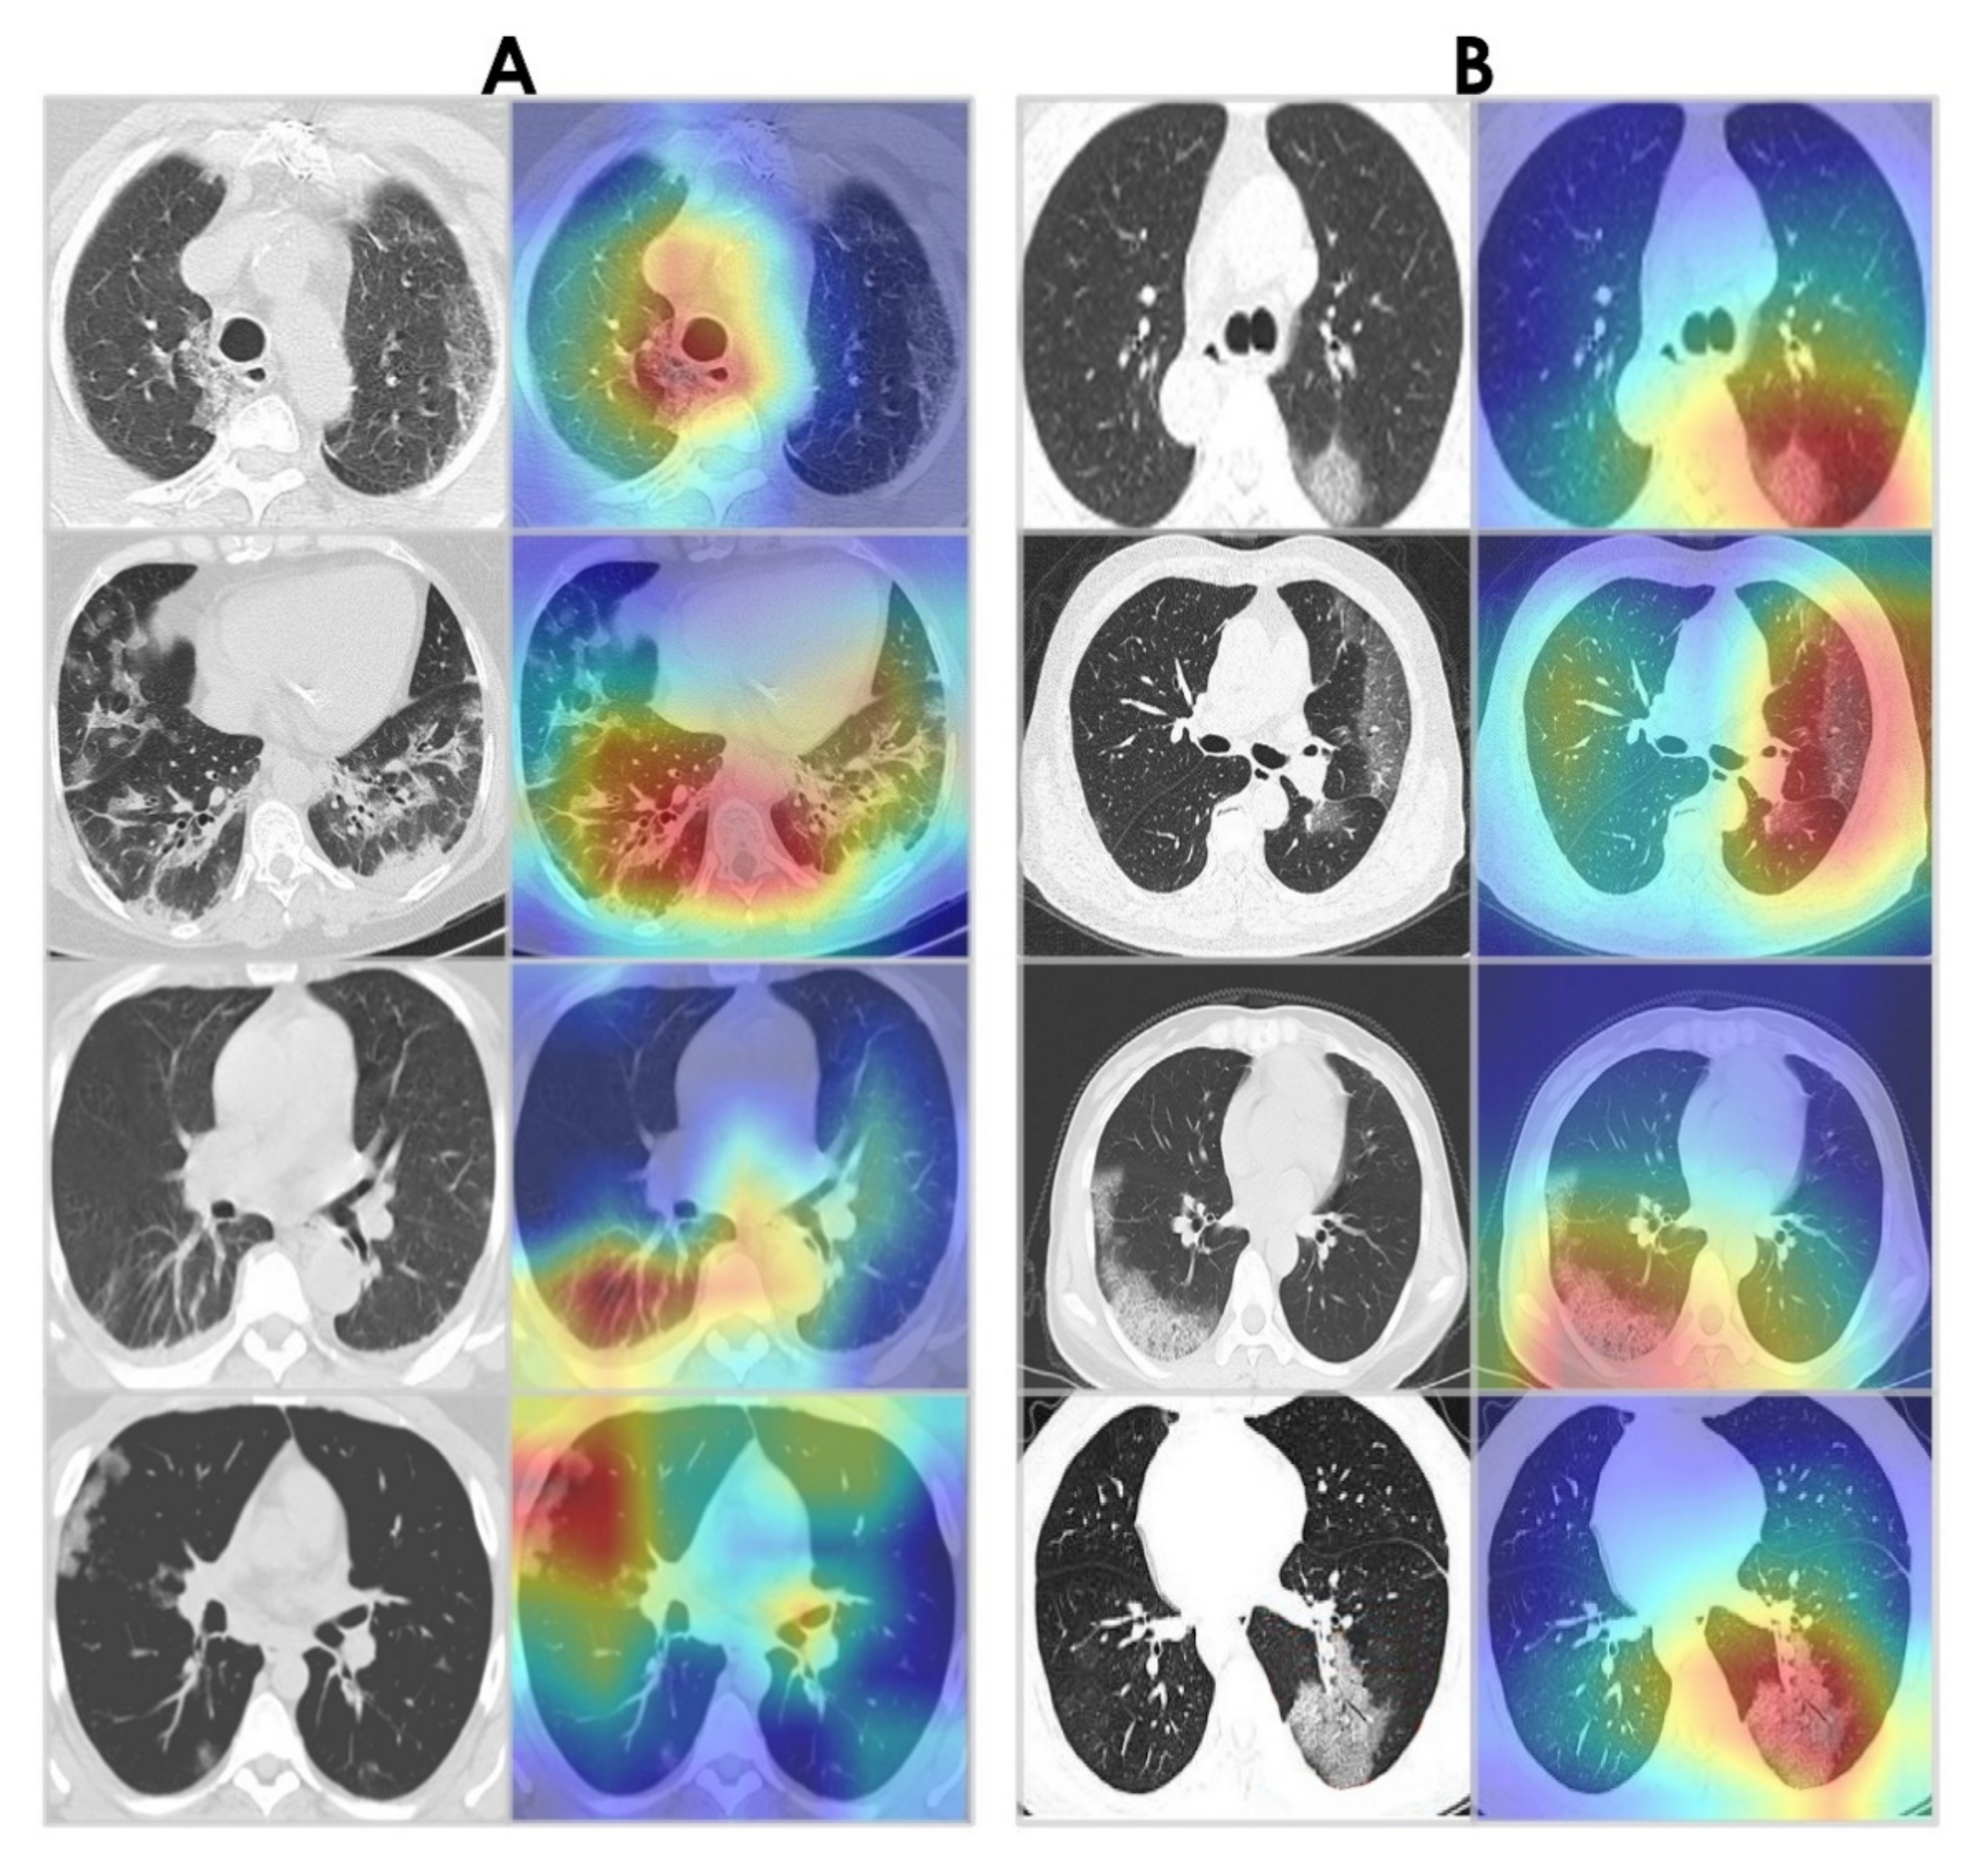

COVID-19 CT Detection Diagram

Prediction of COVID-19 from Chest CT Images Using an Ensemble of Deep Learning Models

Applied Sciences, 2021

Medical Imaging

Applying machine learning techniques for medical diagnosis, including brain tumor segmentation and COVID-19 prediction from medical scans.